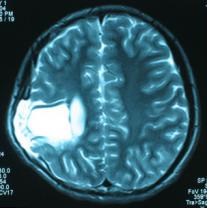

頭顱CT和MRI可見顱骨缺損區(qū)下方軟腦膜囊腫、腦軟化灶或腦室穿通畸形(圖2)。

圖2:①和②CT及骨窗相顯示右頂部顱骨缺損,其下方腦組織呈低密度改變;③-⑥MRI右頂局部顱骨缺如,腦組織輕度向外膨隆,右頂葉側(cè)腦室體部旁局部腦組織缺如,代之以囊性長T1、長T2信號。